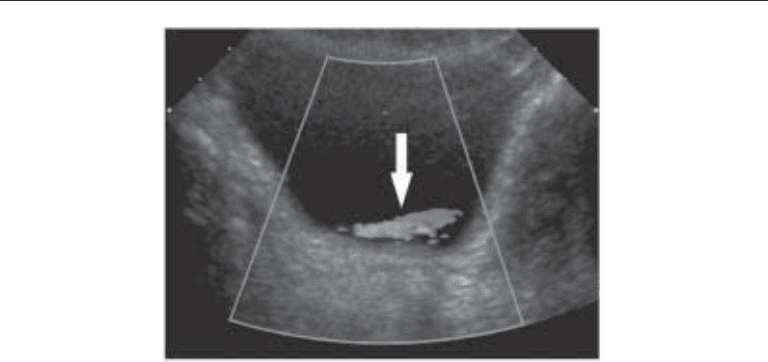

in the prone position to aid in distinguishing a bladder stone from a stone impacted in the

interureteric ridge portion of the ureterovesical junction, which may simulate a bladder

stone on a supine image (53) (Fig. 17). In our institution, noncontrast scans obtained to